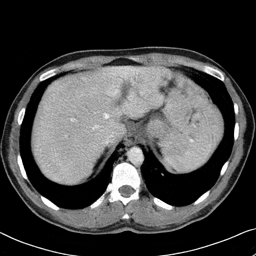

In many clinical settings, the use of both Computed Tomography (CT) and Magnetic Resonance (MRI) is necessary to pursue a thorough understanding of the patient's anatomy and to plan a suitable therapeutical strategy; this is often the case in MRI-based radiotherapy, where CT is always necessary to prepare the dose delivery, as it provides the essential information about the radiation absorption properties of the tissues. Sometimes, MRI is preferred to contour the target volumes. However, this approach is often not the most efficient, as it is more expensive, time-consuming and, most importantly, stressful for the patients. To overcome this issue, in this work, we analyse the capabilities of different configurations of Deep Learning models to generate synthetic CT scans from MRI, leveraging the power of Generative Adversarial Networks (GANs) and, in particular, the CycleGAN architecture, capable of working in an unsupervised manner and without paired images, which were not available. Several CycleGAN models were trained unsupervised to generate CT scans from different MRI modalities with and without contrast agents. To overcome the problem of not having a ground truth, distribution-based metrics were used to assess the model's performance quantitatively, together with a qualitative evaluation where physicians were asked to differentiate between real and synthetic images to understand how realistic the generated images were. The results show how, depending on the input modalities, the models can have very different performances; however, models with the best quantitative results, according to the distribution-based metrics used, can generate very difficult images to distinguish from the real ones, even for physicians, demonstrating the approach's potential.